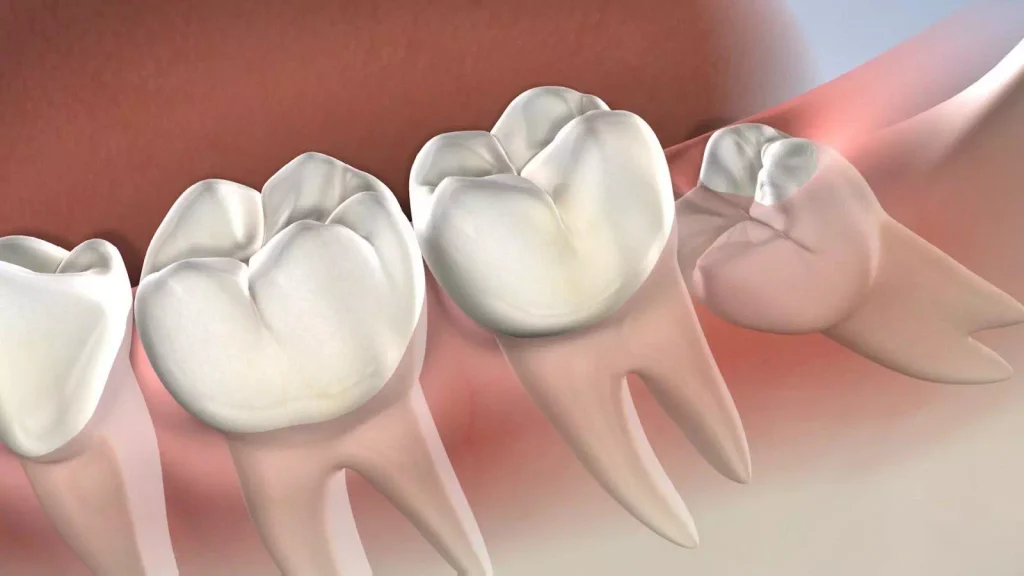

Gömülü diş, genellikle çene yapısının darlığı veya diğer dişlerin yerini kapatması sonucu oluşur. Çene kemiğinin büyüme sürecinde yeterli alan açılmaması, dişlerin normal pozisyonda çıkmasını engeller. Özellikle yirmilik dişler, yani üçüncü azı dişleri, genellikle bu problemle karşılaşır çünkü ağız içindeki en son dişlerdir ve çıkacak yer bulmakta zorlanırlar. Genetik faktörler de bu durumun oluşmasında önemli bir rol oynar; bazı ailelerde gömülü diş problemi daha sık görülür.

Gömülü dişler, sadece çene yapısı ve genetik faktörlerle sınırlı kalmaz, aynı zamanda dişlerin çıkma sürecindeki yönlendirme eksikliklerinden de kaynaklanabilir. Dişler çıkarken yanlış bir açıyla büyüyebilir ve bu da onların diğer dişlerin arkasında veya diş eti altında kalmasına neden olabilir. Bebeklik döneminde dişlerin çıkma sırasındaki problemler, gelecekte gömülü dişlerin oluşmasına zemin hazırlayabilir. Bu nedenle, erken yaşlarda düzenli diş kontrolleri yapmak, ileride oluşabilecek diş sorunlarının önlenmesi açısından önemlidir.